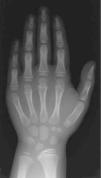

Edad ósea: 6,5 años (Greulich-Pyle). La radiografía practicada con este fin (fig. 2) muestra una imagen de características similares a la de su padre y su hermano (fig. 3).

Figura 2. Radiografía de mano y muñeca solicitada para medir la edad ósea de la paciente.

La imagen de la radiografía de la paciente (fig. 2), muestra la displasia de Madelung de la Discondrosteosis de Leri Weill. La imagen, que solamente comprende carpo y mano, muestra varios signos, aún incompletos por la corta edad de la niña, que orientan al diagnóstico:

1.Deformación de la fila proximal del carpo, en la que el hueso semilunar se ha acercado a la epífisis radial, dando al borde carpal proximal, normalmente curvo, una configuración picuda (piramidal).

2.Distancia radiocubital ampliada (apreciable aquí, entre ambas epífisis).

3.Fusión precoz de la cara ulnar de la epífisis radial.

A los pacientes con hipocrecimiento se les practica una radiografía de muñeca y mano, para medir su maduración ósea. La misma imagen es útil para investigar la posible existencia de la semiología radiológica aquí mostrada. Esto ya es posible en el escolar (aún sin deformidad visible en el antebrazo), y es un valioso instrumento diagnóstico a pesar de su sensibilidad limitada. La eventual identificación positiva debe seguirse del insalvable cariotipo y de la investigación molecular del gen SHOX en el paciente y sus familiares directos.